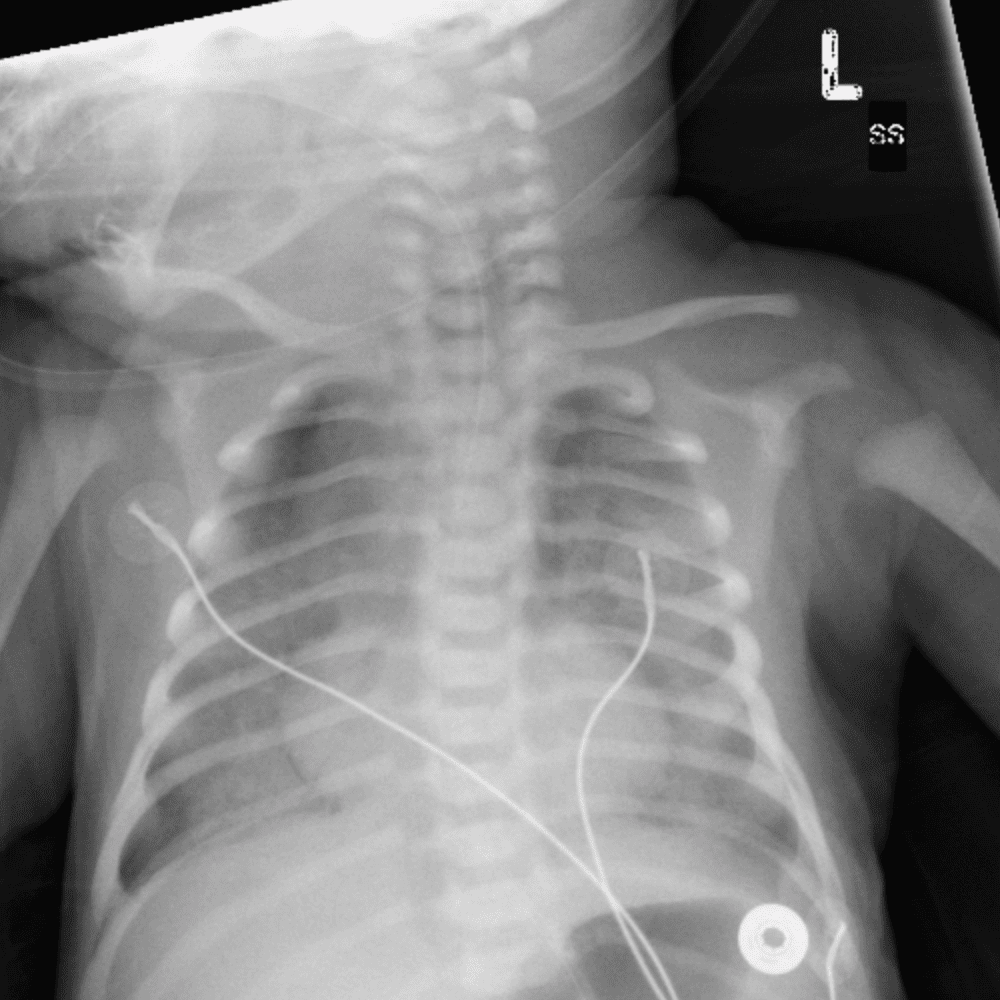

Peds Chest

Practice

Simulates call by including subtle or difficult cases and some normals.

50 cases